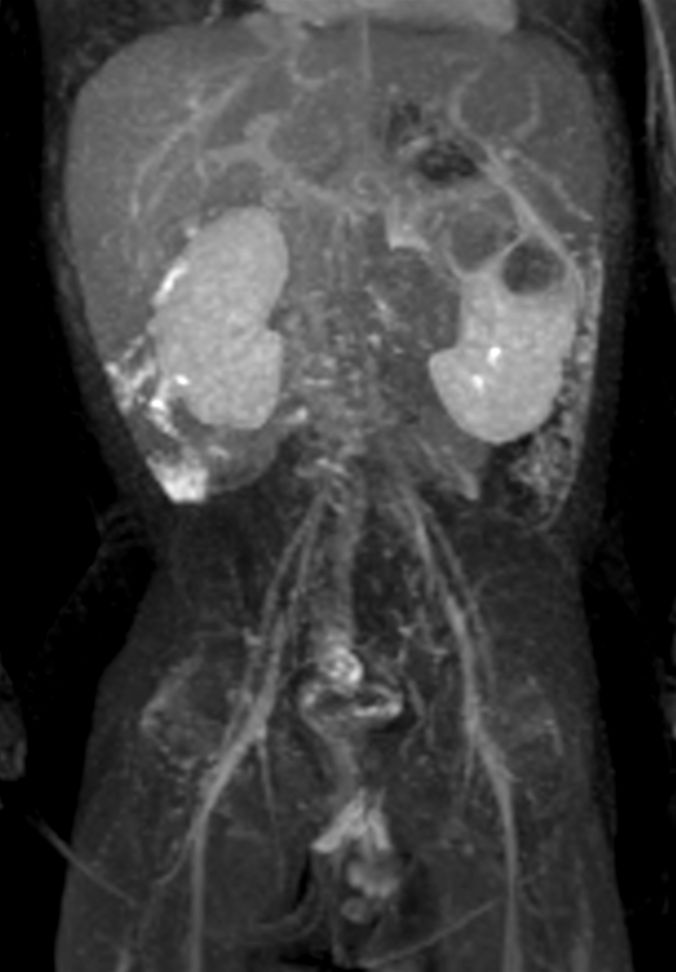

Coronal T2w MultiVane XD